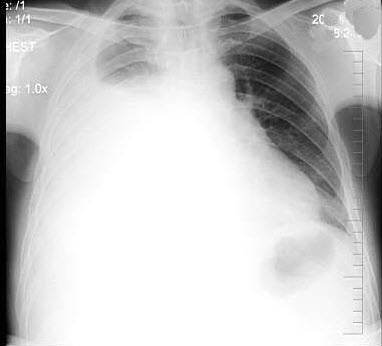

60、单项选择题

男,45岁,HBV阳性10年,胸痛1月余伴咳嗽,咯血1天,胸片如图,最可能的诊断是()

A.肺多发性脓肿

B.肺韦格肉芽肿

C.HBV病毒肺部转移

D.金葡菌感染

E.肺转移瘤